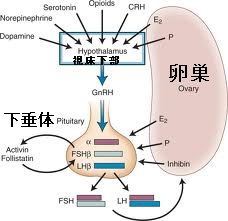

- ゴナドトロピン(性腺刺激ホルモン):性腺(卵巣・精巣)を刺激するホルモン。LH、 FSH、 hCGがあります。

- LH(黄体形成ホルモン):下垂体前葉で合成・分泌され、卵巣ではLHに反応し, 女性ホルモン(エストロゲンやプロゲステロン)が産生されます。精巣ではLHに反応し、男性ホルモン(テストステロン)が産生されます。女性では月経周期の途中のLHサージ(急激なLH上昇)が排卵を誘発します。LHは更に排卵後の卵胞を黄体化させ、プロゲステロンを分泌させます。

- FSH(卵胞刺激ホルモン):下垂体前葉で合成・分泌され、卵巣内の未成熟な卵胞の成長を刺激し成熟させる。男性では、FSHは精巣のアンドロゲン結合タンパク質の産生を刺激し、精子形成を促進。

- hCG(ヒト絨毛性ゴナドトロピン): 受胎の直後から胎盤の一部で作られます。LH(黄体形成ホルモン)と構造が似ており、通常は14日程度で消える黄体を長持ちさせ、妊娠を継続させます。

- GnRH(LH-RH)[性腺刺激ホルモン放出ホルモン(Gonadotropin releasing hormone, GnRH)]:は視床下部で合成・分泌され、下垂体前葉からFSHとLHを分泌させます